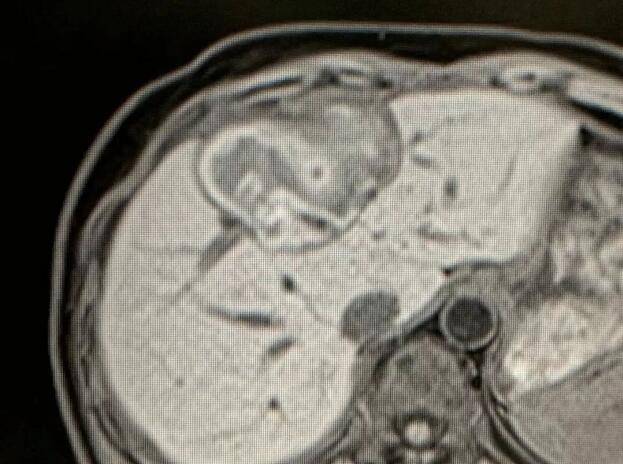

因为肝上的肿瘤比较大 , 血运很丰富 , 所以 , 复大的专家团队首先为她做了介入栓塞治疗 。 然后第二步 , 为她做了冷冻消融 。 接着 , 在椎体上的肿瘤做了冷冻加粒子植入 。

文章图片

做完治疗两周以后 , 再复查CT , 肿瘤基本上都坏死了 。 作为一名影像学专家 , 苏女士自己看了片子以后 , 对自己的治疗效果非常满意 。